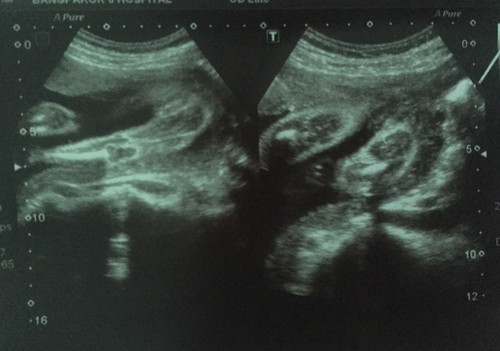

แบบนี้ผู้หญิงใช่มั้ยค่ะ

เห็นเป็นกลีบ น้องผู้หญิงค่ะแม่ ยินดีด้วยนะคะ